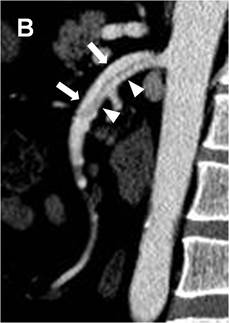

我科自成立以来,在缺血性肠病、肠系膜动脉夹层等方面做了大量的临床与研究工作,发表相关核心期刊文章及SCI文章数篇,并提出Luan式肠系膜上动脉夹层影像学分型指导临床治疗。

图示:Luan式肠系膜上动脉夹层影像学分型